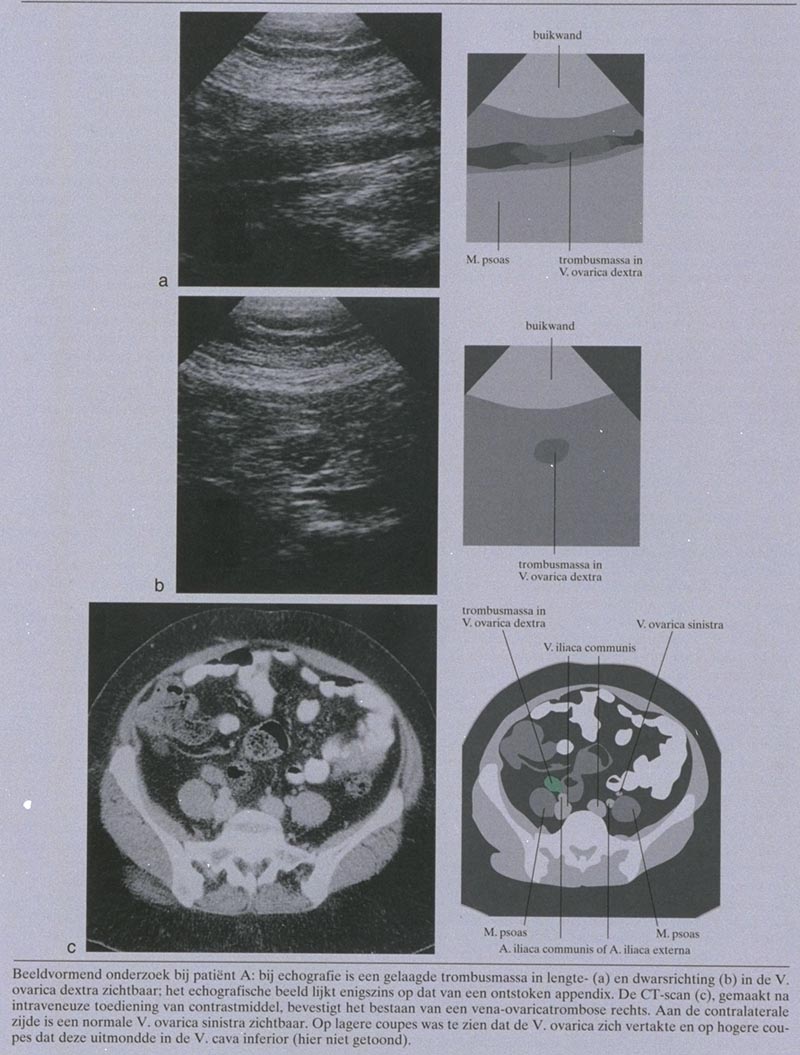

Bij abdominaal en vaginaal echografisch onderzoek werd rechts een structuur gezien passend bij een ongecompliceerd intramuraal myoom met een diameter van 8 cm en normale adnexa. Rechts ventrolateraal van de V. cava inferior werd een verticaal verlopende, buisvormige, concentrisch gelaagde structuur met een diameter van 9 mm waargenomen. De caudale begrenzing begon op het niveau van het rechter adnex, de craniale begrenzing was door storend darmgas niet te visualiseren (figuur a en b).

Differentiaaldiagnostisch werd er nu gedacht aan vena-ovaricatrombose en in mindere mate aan appendicitis. Om de diagnose te kunnen stellen werd een CT-scan van het abdomen gemaakt na intraveneuze toediening van contrastmiddel. Dit onderzoek bevestigde de diagnose ‘vena-ovaricatrombose rechts’ (figuur c).

De diagnose ‘vena-ovaricatrombose’ kan worden bevestigd door (kleuren-Doppler-)echografie en CT na intraveneuze toediening van contrastmiddel.24-6 Een solide tubulaire structuur zonder intraluminale bloedstroom, gelegen in het verloop van de V. ovarica en uitmondend in het infrarenale deel van de V. cava inferior (in geval van trombose van de V. ovarica dextra) of in de linker V. renalis (in geval van trombose van de V. ovarica sinistra), is pathognomonisch voor deze diagnose. De aandoening kan gepaard gaan met perivasculaire ontstekingsverschijnselen.